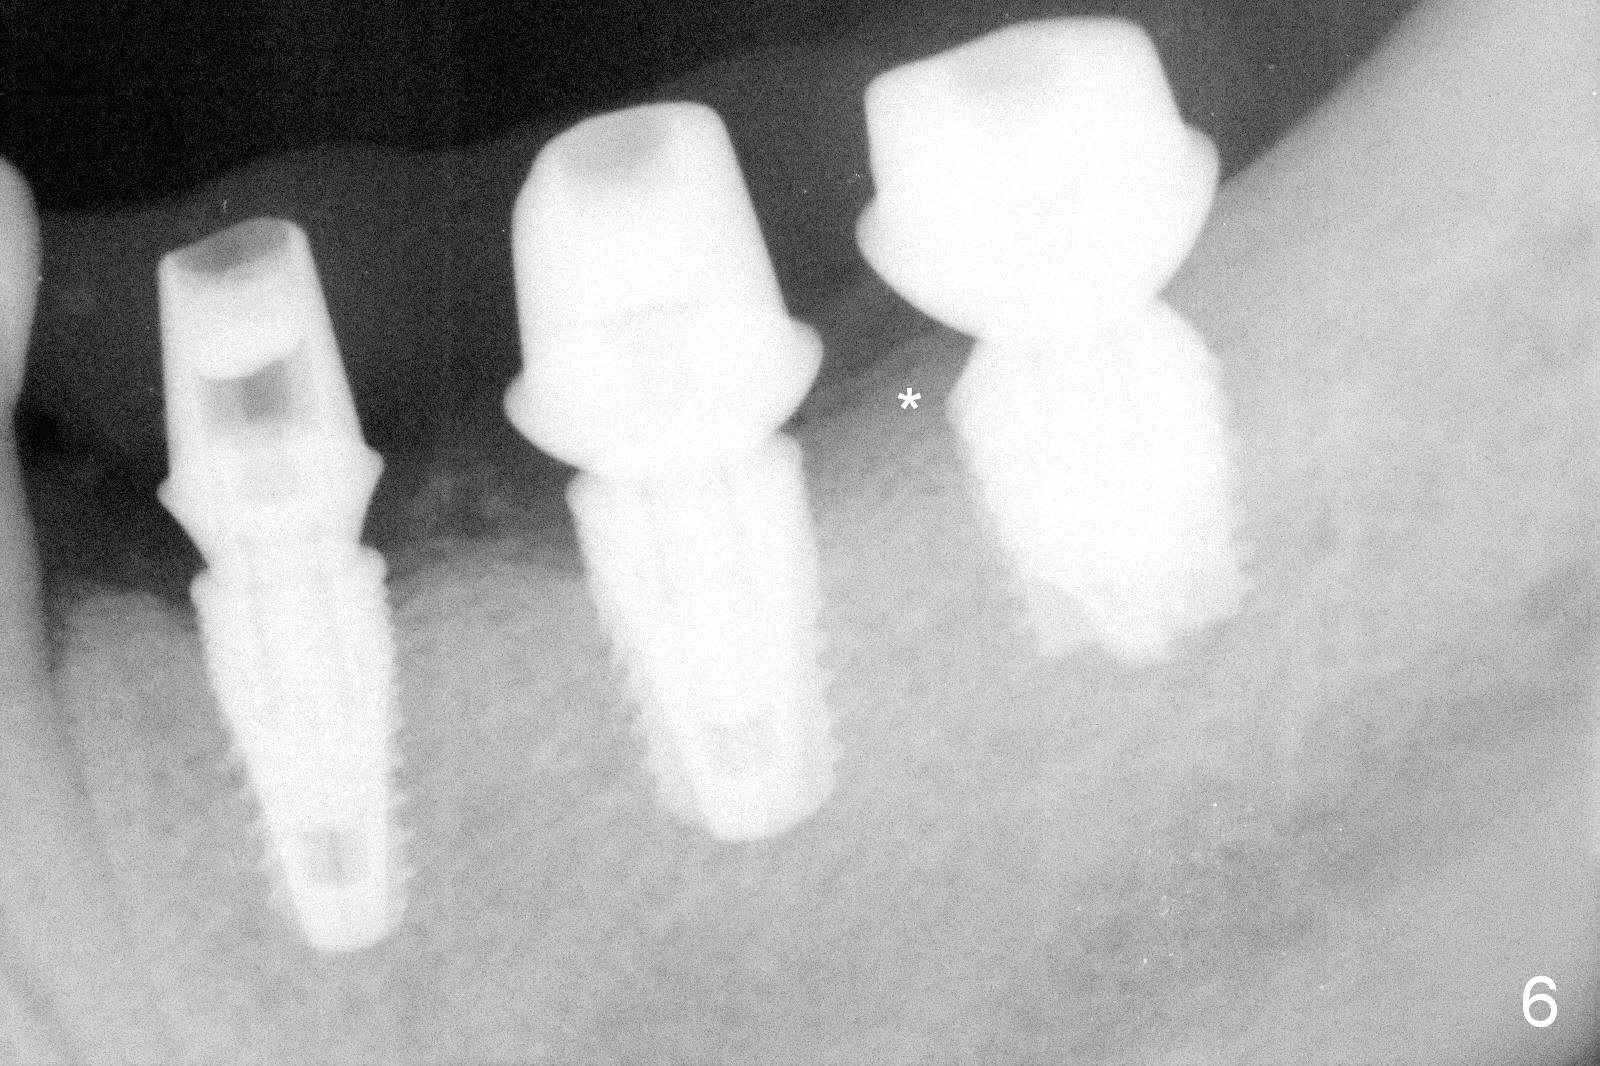

Although bone height is limited, the crest of the lower left area appears to be wide (Fig.1 arrowheads). Initial osteotomy depth is 6 mm (at #18) and 8 mm (19,20) with sufficient clearance from the Inferior Alveolar Canal (Fig.2 red dashed line). The size of the implants at the sites of #18-20 is shown in Fig.3 in millimeters. The insertion torque is around 50 Ncm. When abutments are immediately placed (the diameter and size shown in mm in Fig.4,5) and autogenous bone is packed around the implants/abutments, the ridge looks particularly wide (arrowheads). A splinted immediate provisional is fabricated.

The patient returns for final restoration 4 months postop. He is a smoker with poor oral hygiene. The provisional is fractured at #19 (distobuccal). There is a gap mesial to #18 abutment. It appears that there is mild bone loss, particularly mesial to the implant at #18 (Fig.5,6 *). The implants should have been placed deeper to prevent periimplantitis. When the abutment at #18 (7.8x4(3) mm) is removed, there is food debris mesial, although the gingiva remains healthy. A smaller abutment with shorter cuff is placed (6.8x4(2) mm) before impression.